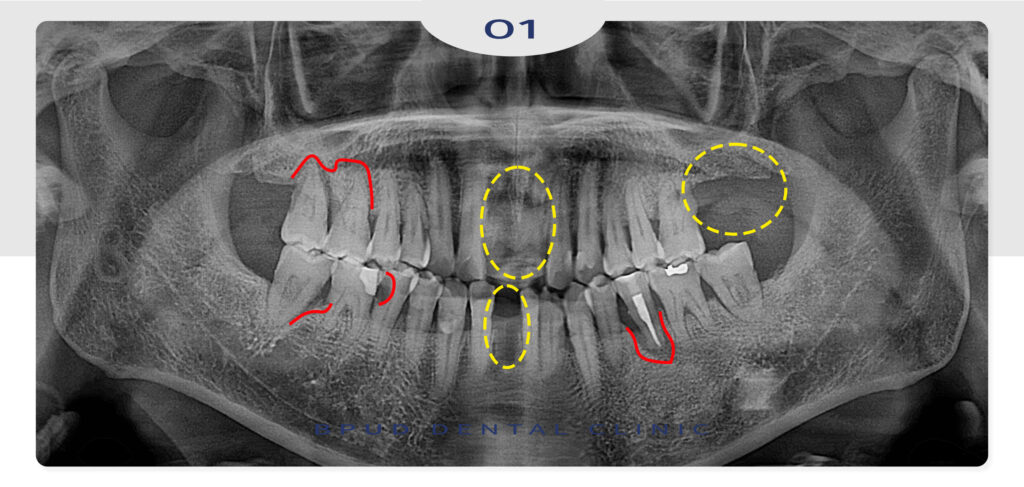

앞니 부위와 왼쪽 부위도 부족한 부분의

잇몸뼈 보충을 위해 상악동 거상술을 동반하여

임플란트 식립을 마쳤습니다.

상악동 거상술은 상악동의 바닥을 들어올려

그 공간에 뼈를 이식함으로써 잇몸뼈의 높이를

확보하는 수술을 말합니다.

상악동의 점막은 매우 얇고 민감하기 때문에

수술 중 천공될 경우 감염이나 이식 실패,

부평임플란트의 실패로 이어질 수 있기 때문에

시술 전 정밀한 CT 촬영과 디지털 장비를 통한

분석을 기반으로 한 치료 계획 수립이 반드시 필요합니다.